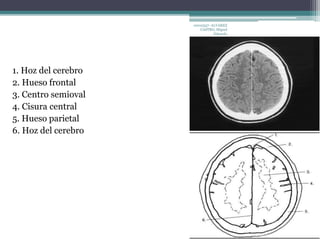

1. Hoz del cerebro

2. Hueso frontal

3. Centro semioval

4. Cisura central

5. Hueso parietal

6. Hoz del cerebro